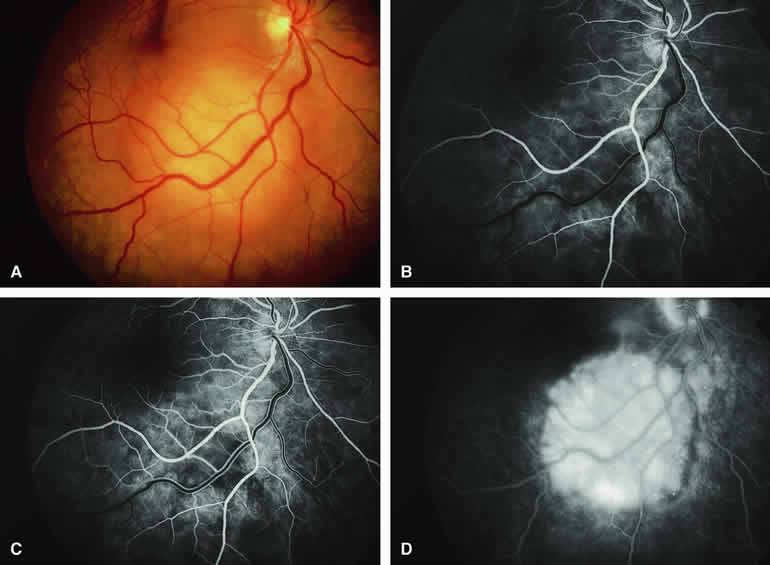

Choroidal Nevus with Drusen and Clumps of RPE Hyperplasia

If a choroidal nevus has drusen and RPE alterations on its surface (see Fig. 4A), fluorescein angiography (Fig. 4B, C, and D) tends to show patchy or stippled window defect hyperfluorescence corresponding to foci of RPE depigmentation, fluorescence blockage by clumps of RPE hyperplasia on the surface of the lesion, and late staining of at least some of the drusen. These features are not usually as evident on ICG angiography as they are on fluorescein angiography.